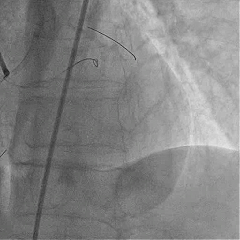

Sion导丝至LCX远端,预扩球囊扩张后,植入支架XIENCEAlpine 2.25*23mm支架一枚

术后造影支架膨胀良好,血流TIMI3级